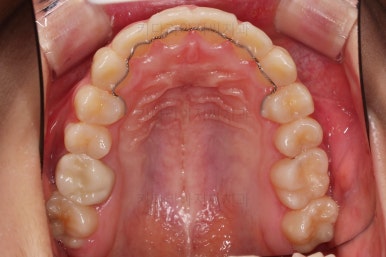

연산동치과 초진 시, 입안의 모습입니다.

보시다시피 앞니쪽이 많이 삐뚤고요. 어금니쪽이 긴밀하지 못한 부정교합이 있네요.

그리고 왼쪽 하단의 사진에 화살표를 보시면, 예전에 신경치료를 해둔 치아인데 어린 나이에 신경치료를 하다보니 크라운으로 치료를 마무리 하지 못했어요.